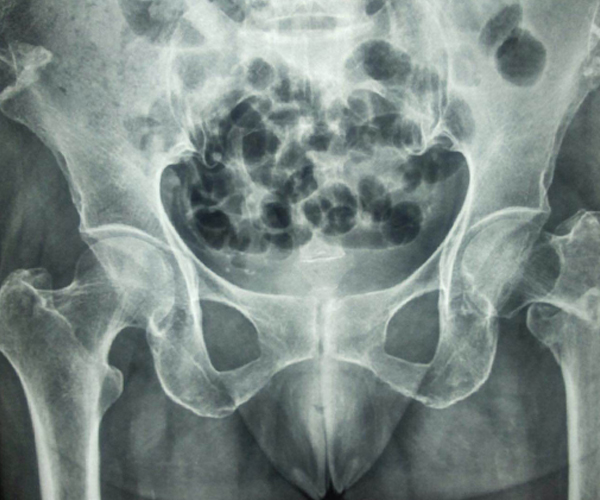

Case:8 Polytrauma

Patient having closed segmented fracture midshaft & lower 1/3 Tibia with closed fracture superior & inferior pubic rami right side with pelvis fracture following vehicular accident wastreated with intramedullary nail for fracture tibia and external fixator for fracture pelvis.

Pre-Op